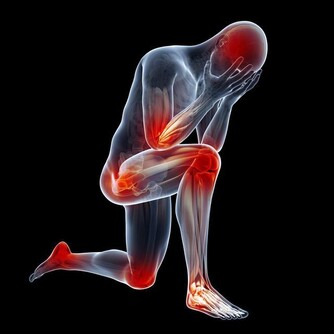

這個階段,女性會出現月經不調、潮熱盜汗、骨質疏鬆、失眠、精神暴躁等症狀,

更年期女性骨質流失相對來說比較嚴重,運動不僅能夠強身健體,也有補鈣的作用,